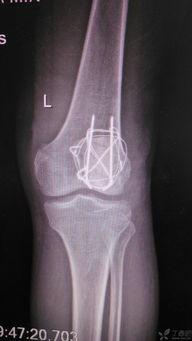

髌骨骨折康复训练视频,视频教程详解与康复步骤

最近是不是不小心扭到了膝盖,疼得你坐立难安?别担心,今天就来给你揭秘一下髌骨骨折康复训练的奥秘,让你在家也能轻松恢复,重拾活力!一、认识髌骨骨折首先,得先了解一下什么是髌骨骨折。髌骨,也就是我们常说的膝盖骨,是人体最大的籽骨,位于膝盖前方。...